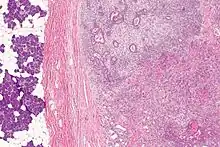

| Micrograph of a carcinoma ex pleomorphic adenoma. The carcinoma component is on the lower right of the image. Benign parotid gland is seen at the left and pleomorphic adenoma is seen at the upper right. H&E stain. | |

Carcinoma ex pleomorphic adenoma (ca ex PA) is a type of cancer typically found in the parotid gland. It arises from the benign tumour pleomorphic adenoma.

Carcinoma ex pleomorphic adenoma is diagnosed by examining it under the microscope with consideration of the individual history.